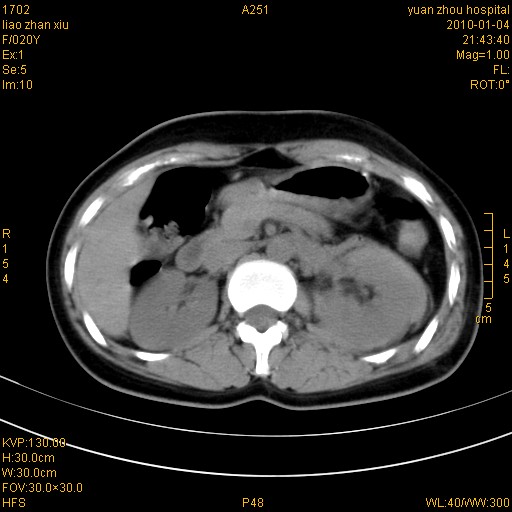

标题: CT23985:F20Y 外伤典型病例 [打印本页]

标题: CT23985:F20Y 外伤典型病例

左肾挫伤,包膜下积血。

左肾挫裂伤伴肾被膜下积血!另:肾周筋膜增厚!

1)左肾包膜下血肿。2)左侧肾挫伤可能;建议:行ct增强扫描检查。3)腰椎左侧横突骨折。

左肾挫伤,包膜下积血,l3、4左侧横突多发骨折。

双侧肾胞膜下出血,左侧较多。l3、4左侧横突多发骨折。

1、左肾挫伤,包膜下积血;

2、l3、4左侧横突多发骨折;

3、腹腔积气,考虑肠管破裂?

左肾挫伤,包膜下积血,L1、2、3、4左侧横突多发骨折。